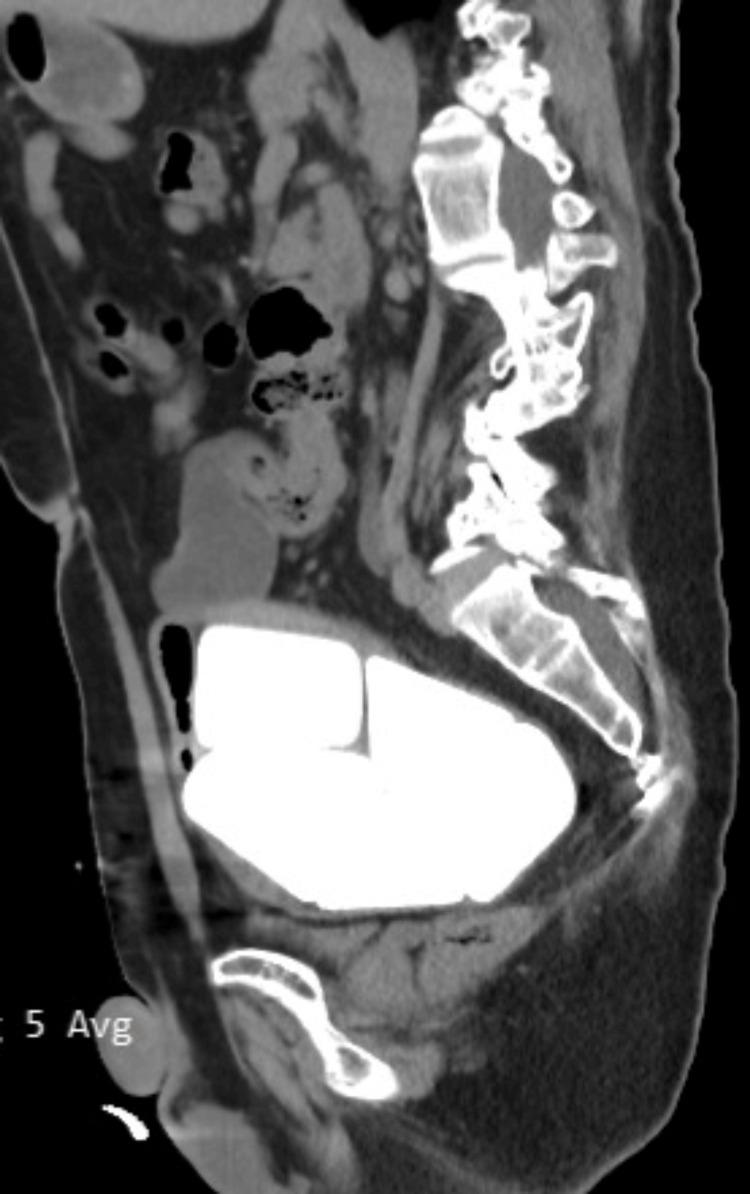

膀胱增大伴多发巨大结石:一例报告

Multiple Giant Stones in an Augmented Bladder: A Case Report.

Bladder stones are a common finding in urology practice although they are less common when compared to kidney and ureteral stones. This case report involves a male patient in his 40s with multiple giant bladder stones. The patient had neurogenic bladder disease due to spina bifida and had a history of bladder augmentation with continent urinary diversion when he was a child. He presented with difficulty in emptying bladder with clean intermittent catheterization. Open cystolithotomy was performed and six giant stones, five pyramid-shaped stones and a cube-shaped stone with a maximum diameter of 7 cm, were removed from the bladder. In our opinion, the rare occurrence of a high stone burden, stone weight and size, and geometric shapes of stones makes this case interesting. The patient was discharged from the hospital on the 10th day after the surgery and there were no postoperative complications.

摘要

膀胱结石在泌尿外科临床实践中较为常见,尽管与肾结石和输尿管结石相比相对少见。本病例报告涉及一名40多岁的男性患者,患有多发巨大膀胱结石。该患者因脊柱裂患有神经源性膀胱疾病,儿童时期有膀胱扩大术及可控性尿流改道术史。他表现为通过清洁间歇性导尿排空膀胱困难。实施了开放性膀胱切开取石术,从膀胱中取出了6块巨大结石,其中5块为金字塔形结石,1块为最大直径达7厘米的立方体结石。我们认为,如此高的结石负荷、结石重量和大小以及罕见的结石几何形状,使得该病例颇具趣味性。患者术后第10天出院,无术后并发症。